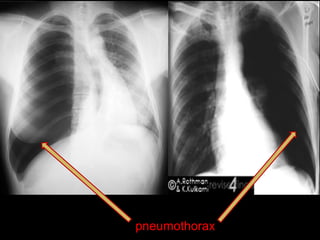

pneumothorax

1) Pneumothorax

2) Bullae

3) Lung cyst

4) Obtructive emphysema

5) Mastectomy

6) Poor technique